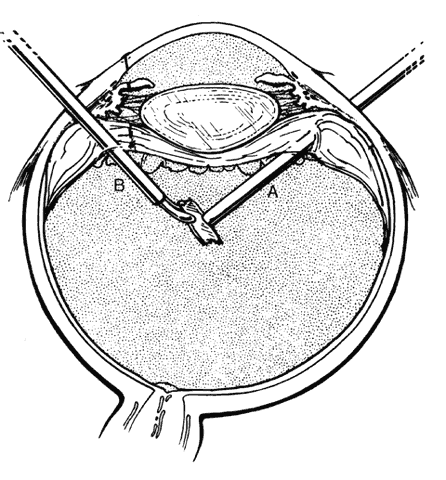

Minor degrees of subluxation should be suspected when phakodonesis or iridodonesis is noted. Zonular rupture is certain if there is vitreous prolapse into the anterior chamber. In the absence of cataractous changes and related visual impairment, treatment is not indicated. A subluxated, cataractous lens can be removed by aspiration-irrigation or phacofragmentation through a limbal incision, but complications may occur, including posterior dislocation of the lens or lens fragments, vitreous prolapse and incarceration, and vitreous aspiration with resultant vitreous base traction and retinal tear formation. Also, visualization of the anterior vitreous by coaxial illumination is poor compared with fiberoptic endoillumination. These problems make pars plana lensectomy an attractive alternative. Bimanual techniques permit fixation and simultaneous removal of the lens by the vitreous suction-cutter, if the lens is soft, or phacofragmentation if it is sclerotic (Fig. 1A). Posteriorly dislocated fragments can be removed safely, with minimal vitreous traction, using the same incisions and instruments (see Fig. 1B). With endoillumination, prolapsed and juxtalenticular vitreous is readily identified and excised with the vitrectomy probe.

Fig. 1. Pars plana lensectomy. A. Infusion cannula in lower temporal quadrant. Lens fixated with myringotomy blade. Vitrectomy probe or phacofragmentor inserted into lens through opposite pars plana. B. Posteriorly dislocated lens fragment removed by standard two-hand technique. (Sternberg P: Trauma: Principles and techniques of treatment. In Ryan SJ (ed): Retina, Vol 3, p 472. St. Louis, CV Mosby, 1989).